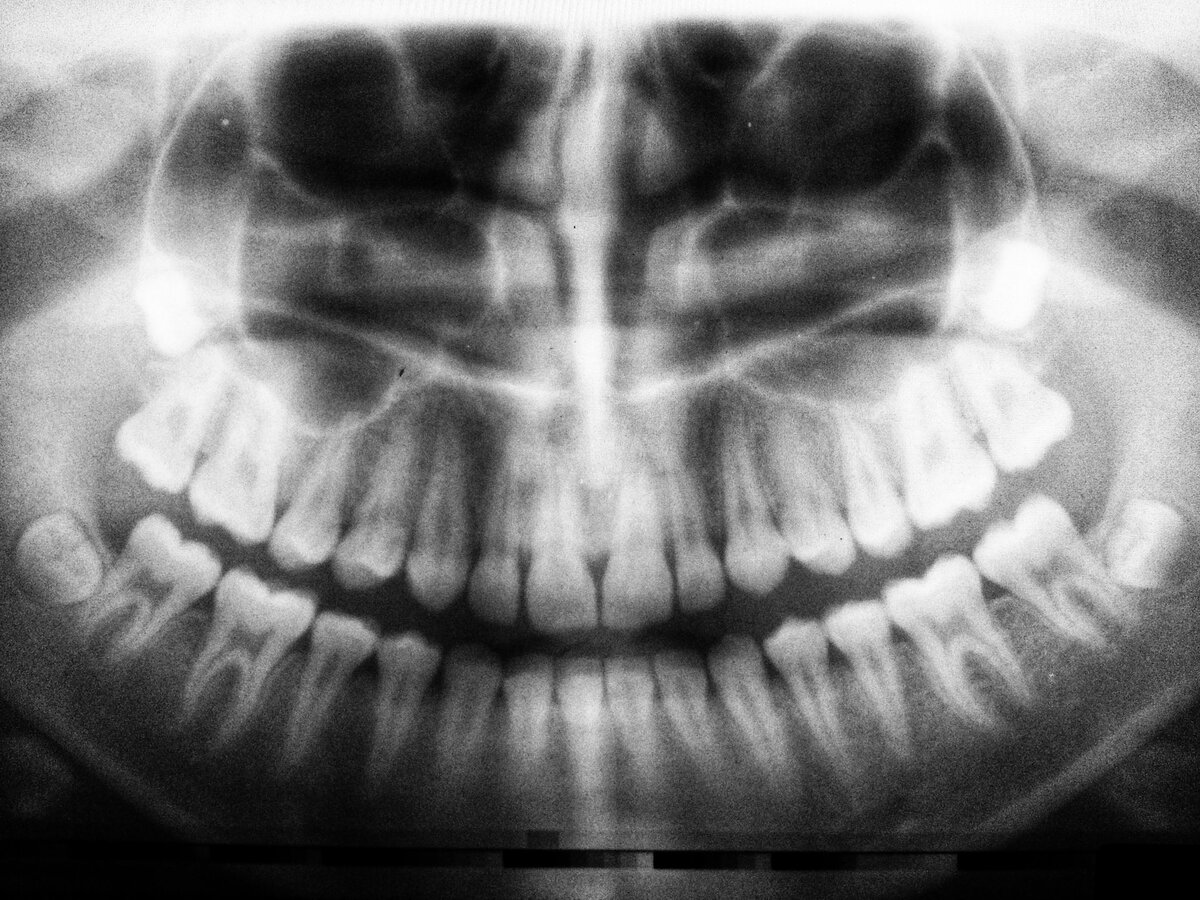

Обзорная панорама

Этот вид рентгена позволяет увидеть помимо панорамы обеих челюстей все окружающие моменты. Такой снимок позволяет оценить общее состояние зубов, найти воспалительные процессы, кисты, костные заболевания, скрытый кариес. Такой снимок даже покажет непрорезавшиеся зубы.